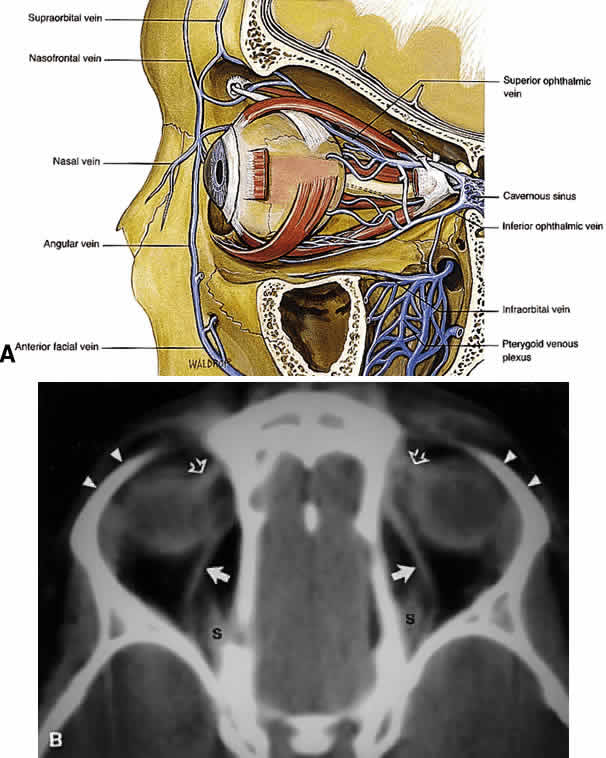

The major venous drainage of the orbit is the superior ophthalmic vein and the CS (Fig. 21). The superior ophthalmic vein follows a medial-to-lateral route posteriorly along the superior orbit, tethered beneath the superior rectus muscle by a fascial sling.19 At the orbital apex, it is usually joined by the inferior ophthalmic vein, which also communicates through more minor branches with the pterygopalatine plexus through the IOF. The central retinal vein typically drains directly into the CS without joining the superior ophthalmic vein. Anteriorly, the orbit also drains into the angular vein of the facial plexus.

Fig. 21. A. Venous drainage of the orbit. Major drainage is supplied by the superior ophthalmic vein, which drains into the CS. Note that the central retinal vein usually drains directly into the CS. Drainage through the pterygoid plexus is minor under normal conditions but becomes very important during outflow problems through the CS (carotid-cavernous or dural-cavernous fistulas). B. Axial CT reveals the course of the superior ophthalmic veins (closed arrows) beneath the superior rectus muscles (S). Also imaged are the superior orbital rims (arrowheads) and the superior oblique muscles (open arrows) as each passes through the trochlea. (A from Dutton JJ: Atlas of Clinical and Surgical Orbital Anatomy, p 79. Philadelphia, WB Saunders, 1994)